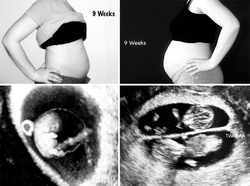

Am făcut câteva fotografii în care se pot vedea diferenţele de dimensiuni ale burţii mele, la fiecare dintre sarcini, dar şi dintre cei mici, în burtică, în diferite etape ale dezvoltării. Eu şi soţul meu încă suntem uimiţi de drumul pe care a trebuit să îl parcurgem pentru a avea copiii pe care astăzi îi ţinem în braţe. Nu aş schimba nimic, în ciuda durerilor şi a stresului prin care am trecut! Cei trei copii ai noştri, acum de 5 şi respectiv 2 ani şi jumătate, sunt lumea mea şi miracolele pe care nu le-aş fi trăit niciodată, dacă medicina nu ar fi fost atât de avansată. Pentru asta, suntem extrem de recunoscători!